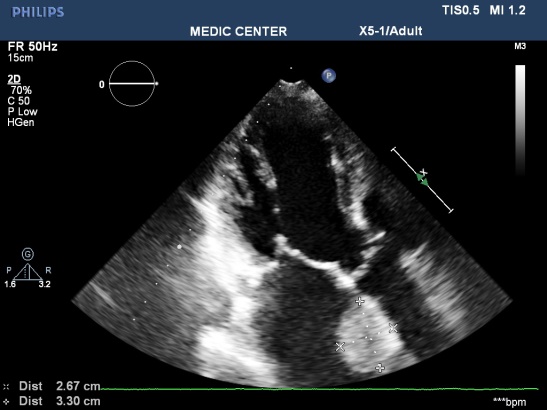

Figure 1. Mitral stenosis with thrombus of LA; “TTE image from Nguyen Tuan Vu”

Features of LV thrombus on echocardiography: a mass with dense echogen, defined margin located adjacent endocardium but distinct from endocardium, existing at least in 2 views (Figure 9).

Figure 9. Apical thrombus in patient with MI; “TTE image from Nguyen Tuan Vu”